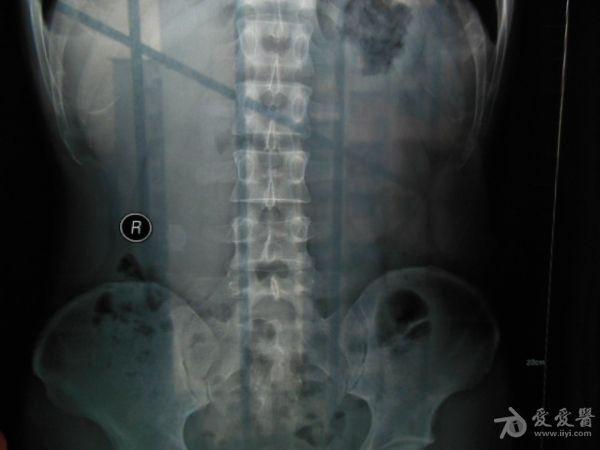

请老师看看这个腰椎和盆骨的平片有无问题

摔了一跤右臀着地,同时闪到腰,查出有椎间盘突出,目前是右臀麻木,整个右腿酸胀沉重。肌力正常走路正常,坐不到5分钟右腿就酸胀难忍。明显觉得左右**感觉不一样,右边软得多,

自觉下腰和盆骨感觉别捏,有歪斜感,扭腰时觉得舒服。腰4右侧一下有异物感。今天照了个腰椎正侧位和盆骨的正位平片,医生说没什么问题,拿来请各位老师看看腰椎和盆骨有没有错位,旋转,不等高等情况,再次感谢。

照该片看应该是骨盆旋移

这种症状拍平片没有什么意义,选择MRI或者CT吧

看片子没发现什么大的问题,没有骨折,没有增生。腰椎间盘突出做核磁共振最清楚。